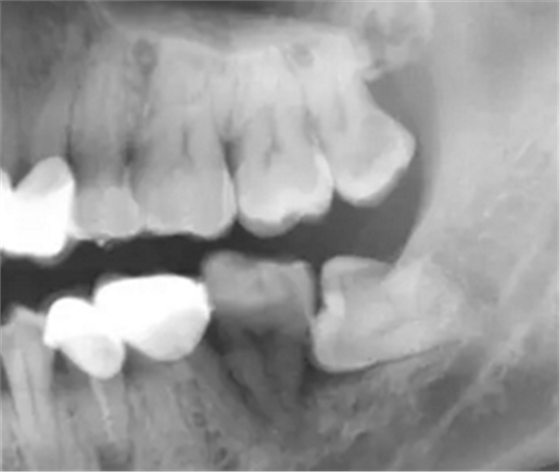

防治:牙拔除術(shù)后應(yīng)仔細(xì)清理牙槽窩,特別是慢性根尖周炎的患牙,根尖炎性病灶不刮治干凈,即可發(fā)生拔牙術(shù)后出血,也可形成慢性炎癥而長(zhǎng)期不愈。多根牙拔除時(shí)應(yīng)防止殘根遺留。如發(fā)生慢性感染,應(yīng)拍攝X線片,了解牙槽窩內(nèi)病變情況,是否有異物遺留,牙槽窩的愈合情況等,然后在局麻下,重新進(jìn)行牙槽窩的刮治,讓血液充滿后,消毒紗布棉卷壓迫止血,并給予口服抗生素治療。